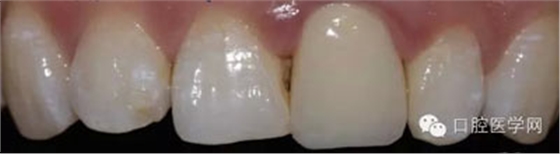

3、由北京精藝義齒工作室高級(jí)技師靳曉輝老師制作的全瓷冠

5、3MU200樹(shù)脂粘接劑粘固全瓷冠術(shù)后照

6、術(shù)后一周照,牙齦恢復(fù)良好